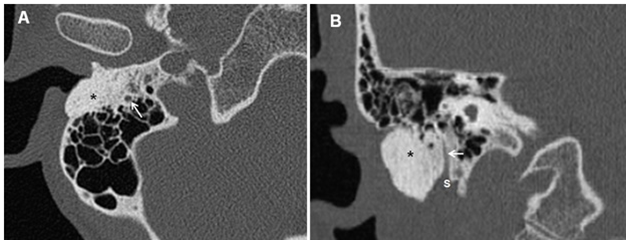

A 43year old female, previously healthy, was referred to our center due to a long-standing history of right recurrent otitis externa that become very frequent and invalidating. She reports also progressive right sided hearing loss. There were no accompanying symptoms ofvertigo or tinnitus in her medical history. Otolaryngologic examination revealed a hard, immobile, mildly tender mass with erythematous overlying skin filling the right EAC, occluding view to the tympanic membrane. The left ear was normal. Facial nerve examination was intact bilaterally. No other masses were palpated in the head and neck region. On audiogram, right conductive hearing loss was revealed. A temporal bone CT scan indicated a well demarcated, dense, sclerotic mass of approximately 2.3x2cm of the right mastoid process filling the EAC and extending inferiorly to the SMF, the mass was very near but not involving the mastoid segment of the fallopian canal. The middle and inner ear were normal. The radiologic appearance was suggestive of osteoma (Figure 1). Because of the severity of her symptoms, especially severe and refractory otitis externa, the patient was asking for definitive treatment. An extensive discussion was done with her on the risk of facial nerve injury because of the critical localization of the lesion. The patient accepted the risk and signed a medical consent of high risk of postoperative facial palsy.

Figure 1 Right Temporal bone CT scan, Axial cut (A) and saggital cut (B) showing a hyperdense bony mass (O) occluding the ear canal extending posteriorly into the mastoid in close relationship with the facial nerve(white arrow) and inferiorly to the stylomastoid foramen (S).